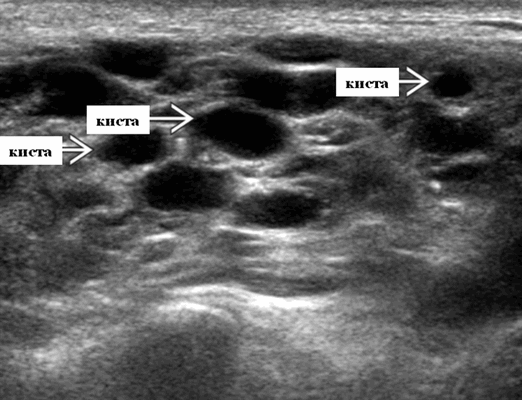

Доброкачественные лимфоэпителиальные поражения (ВИЧ) на УЗИ слюнных желез

- Серошкальное УЗИ. Спектр сонографических находок от простых кист до смешанных и солидных образований. Кистозные, смешанные и солидные поражения могут возникать одновременно в околоушных железах. Кистозные поражения (кисты ДЛК). Хорошо очерченная киста, разного размера, от анэхогенной до гипоэхогенной структуры с задним акустическим усилением. Сеть тонких перегородок ± муральные узлы. Часто встречаются внутренние эхо, которые могут быть мобильными. Сотовидная внешность паренхимы околоушной железы, когда она диффузно изменена з а счет кист. Смешанные поражения (ДЛП). Границы могут быть плохо очерченными, разного размера. Структура преимущественно гипоэхогенная, железы могут быть неоднородными. Без заднего акустического усиления. Солидные поражения (околоушная лимфаденопатия). Множественные овальные / круглые, гипоэхогенные, внутрипаротидные лимфоузлы на УЗИ. Четкий корковый слой ± сохранная корневая архитектура. Сопутствующая реактивная шейная лимфаденопатия

- Цветной допплер. Кистозные поражения: от бессосудистого до умеренного сосудистого кровотока в перегородках, интрамуральных лимфоузлах и на периферии. Смешанные поражения: переменная, васкуляризация от легкой до умеренной. Солидные поражения: внутрипаротидная васкуляризация.